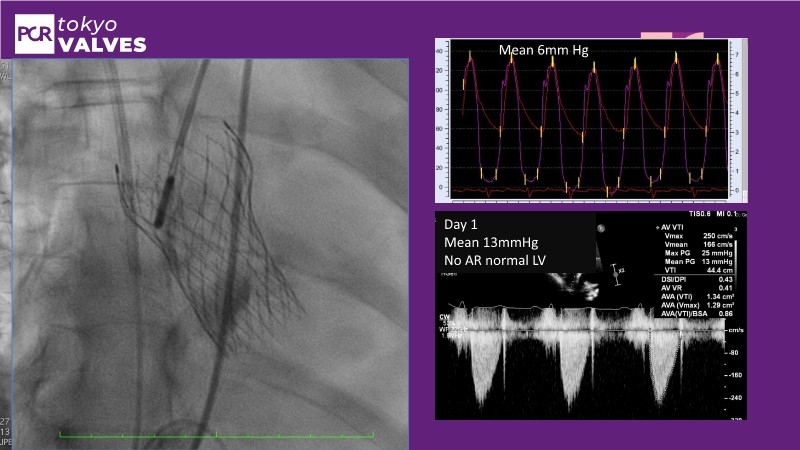

In this expert-led session, explore new frontiers in TAVI, focusing on bicuspid aortic valves, small annulus, and the risk of secondary interventions. Gain insights from the latest randomized trials (RHEIA) and registry data (CAvEAT), with real-world case discussions highlighting their clinical impact.

- To discuss the new frontiers in TAVI including the treatment of patients with bicuspid aortic valve, small annulus and risk of secondary intervention

- To discover the results of latest randomised clinical trials (RHEIA) and registry data (CAvEAT) in these TAVI subsets

- To understand the clinical impact of these data sets through case presentations